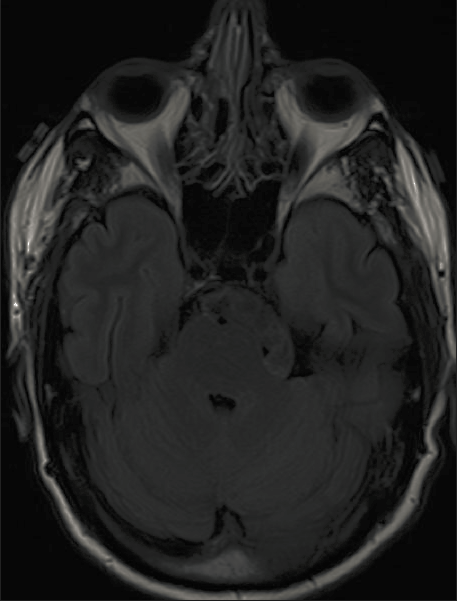

亮度调低

而当γ大于1时,原本就比较暗的图像变得更暗,基本上无法观察了。